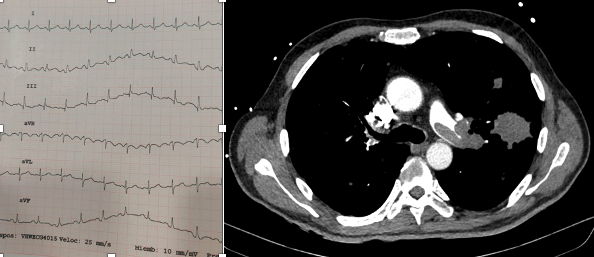

🖥️ PROMISE TOOL

✔️ 5 items

⚡C-index 0.79

📉 84 vs 33% 🔝vs ⬇️ risk